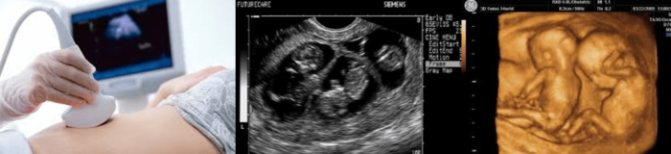

Какие параметры исследуются на ранних сроках, что видно на фото УЗИ?

Как выглядит двойня на ранних сроках? Поначалу врач видит только два темных пятнышка. Кроме того, отчетливо прослушивается биение двух сердец, видны две плаценты и два амниотических пузыря. На фото можно увидеть снимок УЗИ близнецов.

На ранних сроках при проведении УЗИ оцениваются следующие параметры плода:

- копчико-теменной размер — КТР, близнецы обычно имеют меньшие размеры, чем одиночные эмбрионы, и к 12 неделе достигают роста 6 см и массы тела 8 г;

- бипариетальный размер — БПР, расстояние между височными костями черепа;

- частота сердечных сокращений — 110-150 уд/мин;

- сформированность нервной трубки;

- наличие носовой косточки;

- толщина воротникового пространства — его расширение вместе с уменьшением носовой косточки указывает на синдром Дауна;

- сформированность внутренних органов.

Нередко на снимке УЗИ заметно, что один эмбрион меньше другого. Если расхождение невелико и составляет всего лишь несколько миллиметров, то беспокоиться не нужно, размеры выровняются или в процессе беременности, или после рождения малышей.